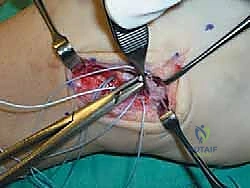

الخطوة السادسة: خياطة وشد الأربطة (إجراء بروسترم الأساسي)

يتم تمرير الخيوط الجراحية القوية عبر الأربطة الممزقة (ATFL و CFL) والكبسولة المفصلية. أثناء عقد هذه الخيوط، يتم وضع الكاحل في وضعية الانقلاب الخارجي (Eversion) والانعطاف الظهري (Dorsiflexion) لضمان شد الأربطة بأقصى درجة ممكنة، مما يعيد للكاحل ثباته الفوري.

الخطوة السابعة: تعديل جولد (The Gould Modification) - سر القوة الإضافية

لضمان عدم تكرار التمزق، خاصة للرياضيين، يضيف الجراح خطوة "تعديل جولد". تتمثل هذه الخطوة في سحب جزء من النسيج الليفي القوي المجاور والمسمى بـ "القيد الباسط السفلي" (Inferior Extensor Retinaculum) وخياطته فوق الأربطة التي تم إصلاحها. يعمل هذا النسيج كـ "حزام أمان" إضاف